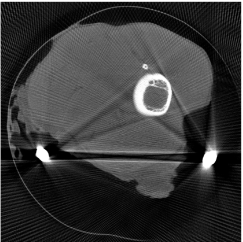

The proposed re-weighted JSR model requires a pre-estimation of the metal trace and weights in projection domain. They can be obtained fairly easily from a roughly reconstructed CT image using a simple reconstruction model. In this paper, we use the tight wavelet frame based analysis model [8]. This subsection describes the details on how metal trace and weights are computed using the NURBS-based cardiac-torso(NCAT) phantom [45]. Two metal components are implanted in the NCAT phantom as shown in Figure 1(a) and the simulated projection data is obtained from a multi-chromatic X-ray source. Details on the settings of the imaging system are postponed to Section 4.1.1.

The optimization problem (2.12) can be solved by the split Bregman algorithm [29, 8] efficiently, which is also equivalent to the alternating direction method of multipliers (ADMM) [24, 26, 28]. The reconstructed phantom image by model (2.12), denoted by , is shown in Figure 1(b). Metal location in image domain can be robustly estimated by the summation of the high frequency wavelet frame coefficients (Figure 1(c)) followed by a simple thresholding. Then, the index of the metal trace in Radon domain, denoted by , can be identified by the projection of the indicator function associated to the metal location (Figure 1(d)).